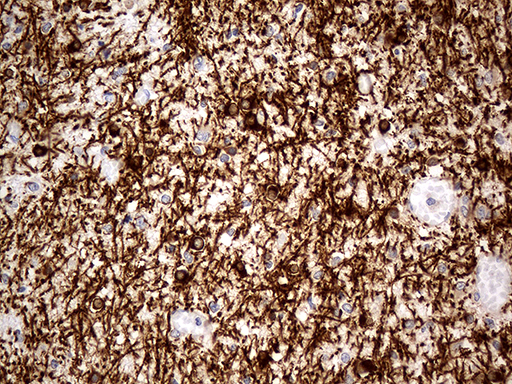

Immunohistochemical staining of paraffin-embedded Human embryonic cerebellum within the normal limits using anti-CNP mouse monoclonal antibody. (Heat-induced epitope retrieval by 1mM EDTA in 10mM Tris buffer (pH8.5) at 120°C for 3min, M01017-4) (1:500)